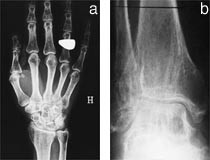

MR cerebrum viste utvidede ventrikler, grovt overflaterelieff og noe økt signalintensitet periventrikulært (fig 2). Skjelettrøntgen av hender og føtter viste cystiske oppklaringer i en rekke knokler (fig 3). Det var også mulig cystedanning i trochanterregionen og en usikker cystedanning i buen av C1. Det ble for øvrig ikke funnet cyster i aksialskjelett, dvs. cranium, columna, thorax og bekken. Ved histologisk undersøkelse av cystemateriale fra finger fant man et bilde som svarer godt til det som beskrives ved PLO-SL (fig 4). EEG viste abnorm aktivitet frontotemporalt bilateralt. Det var ingen epileptiform aktivitet. ”Brain stem auditory evoked response” (BAER) var unormal på venstre side, med ikke-reproduserbare potensialer ved repetert undersøkelse. Normal ”visual evoked response” (VER) og ”somatosensory evoked response” (SER). I spinalvæsken fant man forhøyet totalprotein, 0,73 g/l. Ved nevropsykologisk testing var det tydelig subnormal generell funksjon, med nedsatt sensorimotorisk funksjon, redusert psykomotorisk tempo, uttalt svekkelse i hukommelsen, særlig for verbalt materiale, og perseverasjonstendens. Resultatene antydet at svekkelsen var relativt størst for funksjoner knyttet til venstre hemisfære. Man konkluderte med at utfallene var forenlige med betydelig grad av demens.

De radiologiske skjelettforandringene oppstår allerede i barndommen, men oppdages hyppigst i 20 –30 -årsalderen i forbindelse med traumer (6). Lesjonene opptrer som multiple, symmetriske, ikke-ekspansive cyster uten sklerotisk begrensning og med lokalisasjon i de epifysære og metafysære områder av de lange knokler, i patella og i alle hånd- og fotknokler. Talus er hyppigst affisert, ofte med uttalte cystiske lesjoner. De gjenværende trabekler har en longitudinal anordning. Mineraltettheten av beincortex er redusert. Det er hittil ikke funnet tilfeller med affeksjon av de aksiale deler av skjelettet.

Pasient 2 viste alle disse trekk (fig 3), mens det for pasient 1 kun forelå røntgenbeskrivelse av multiple cyster distalt i underarmene og i håndskjelettet.